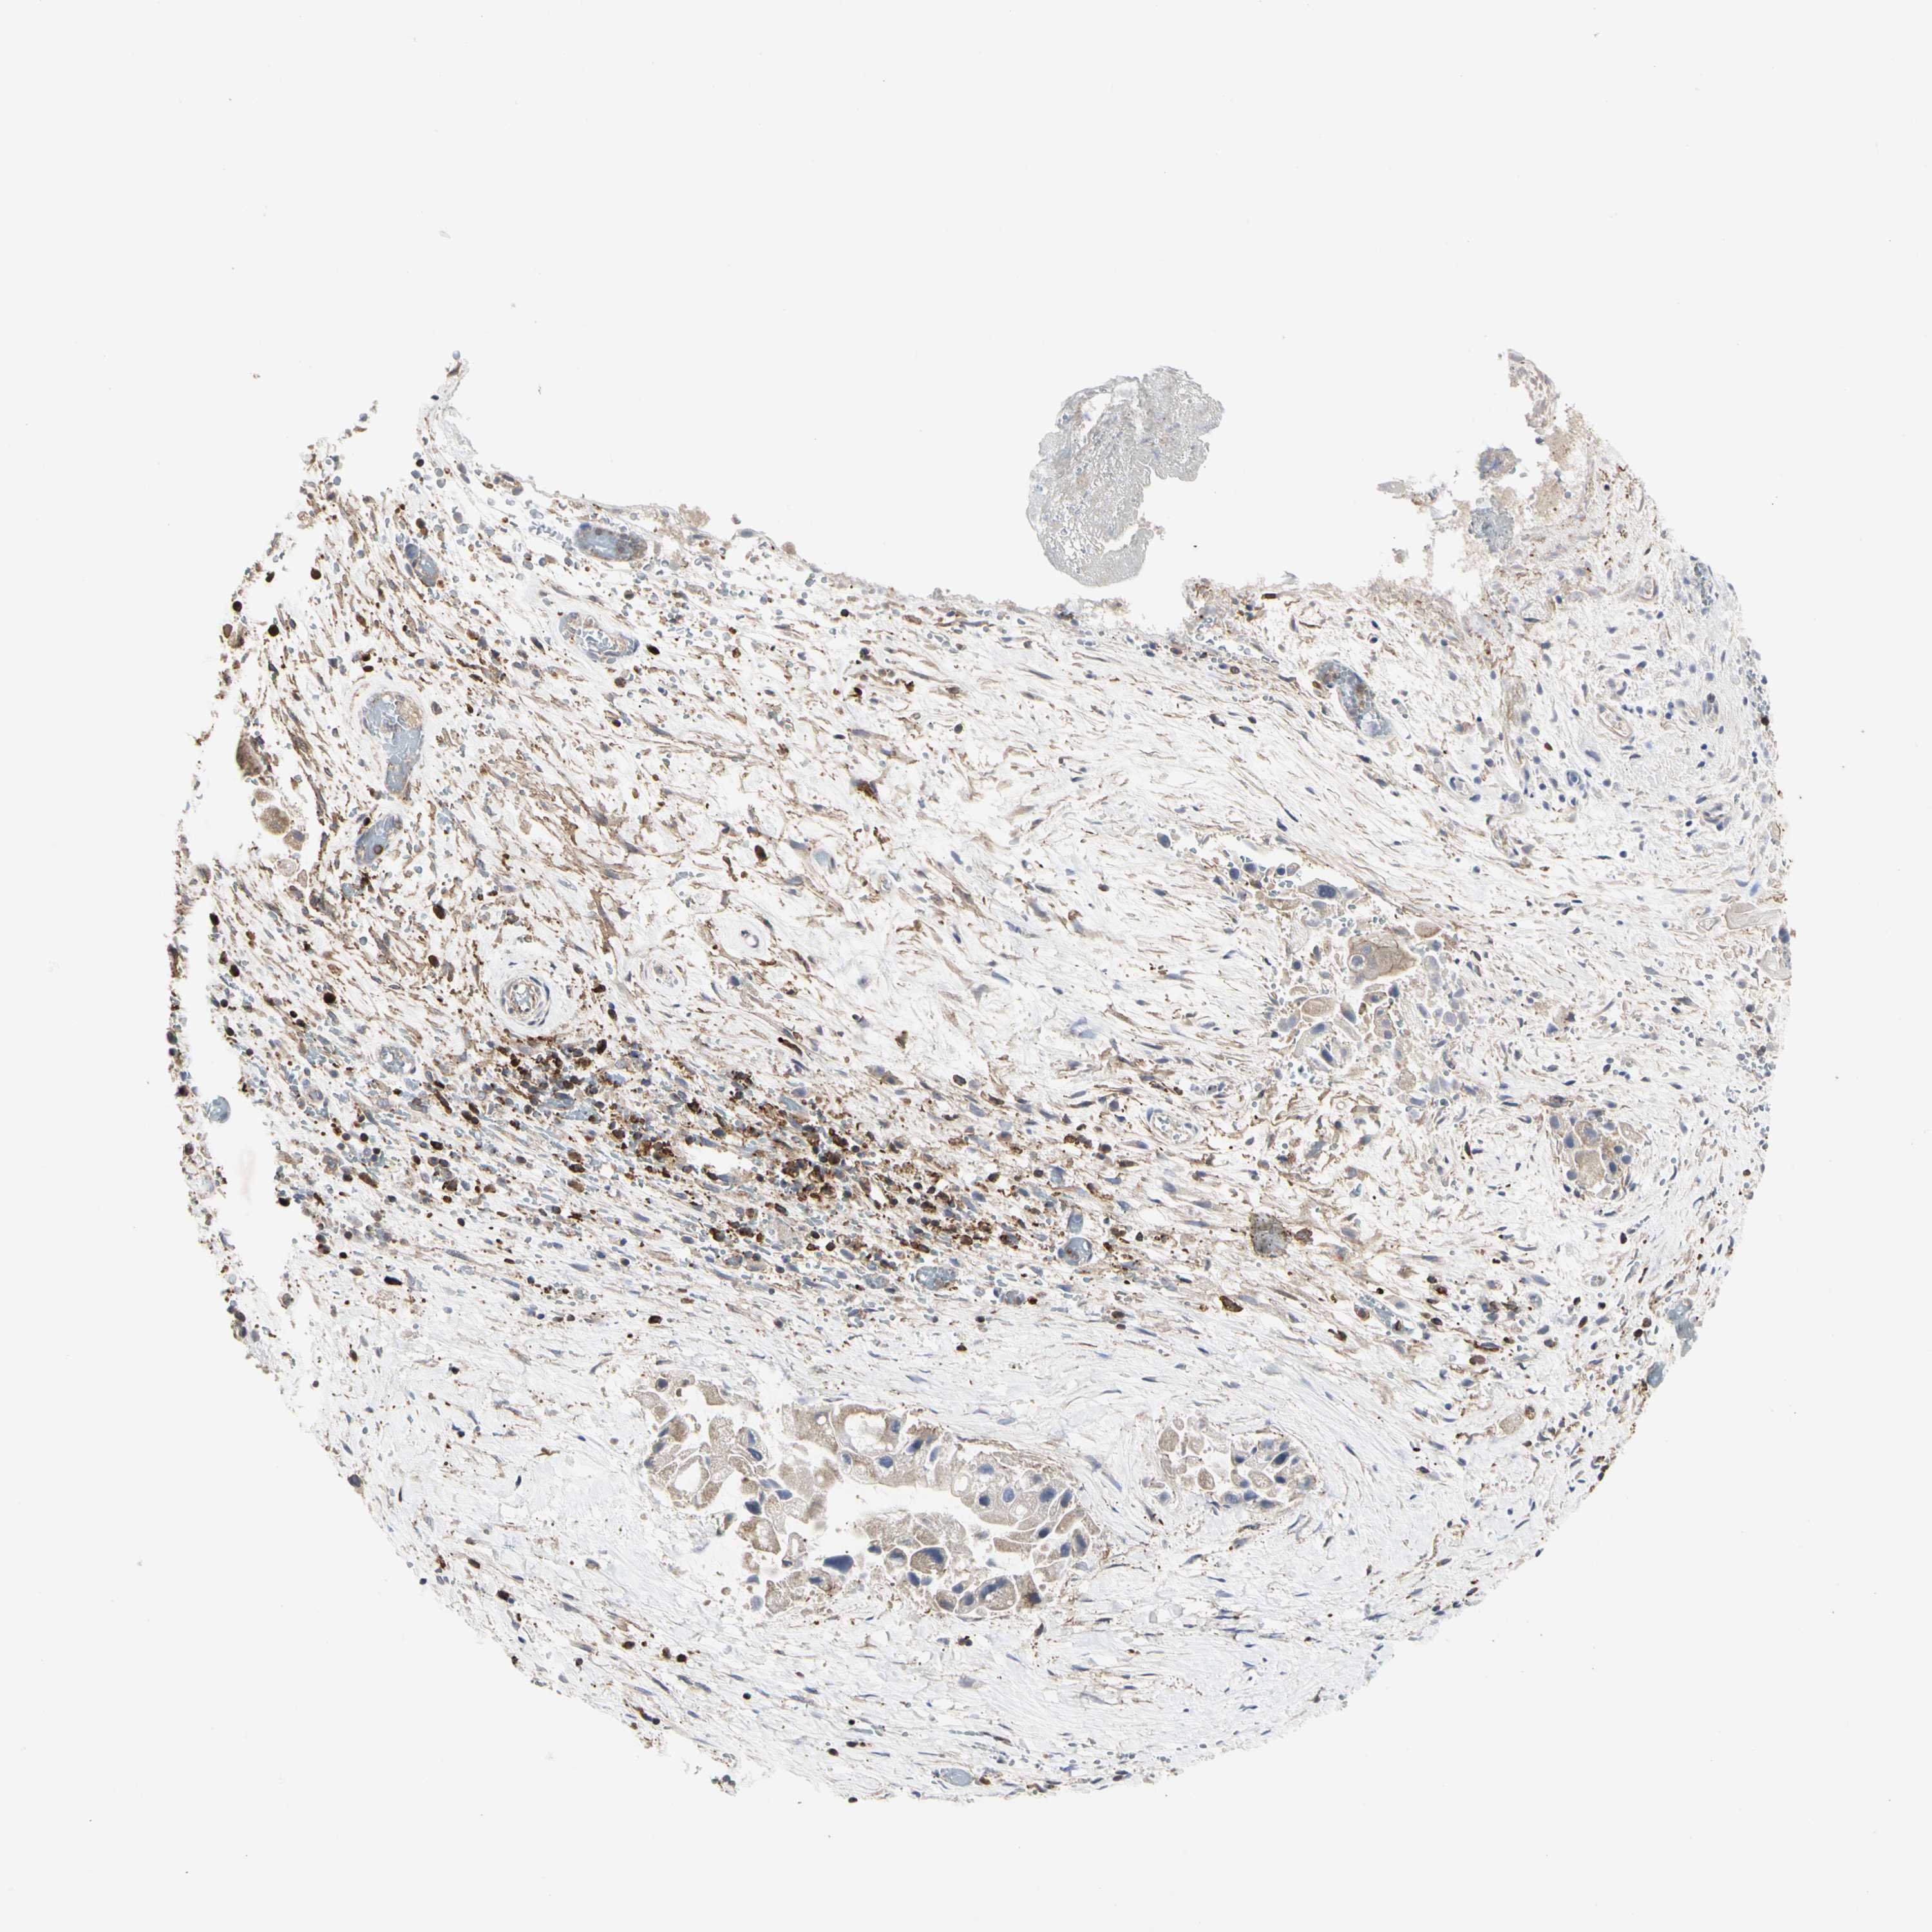

LIVER CANCER - Protein expressioni

A mouse-over function shows sample information and annotation data. Click on an image to view it in a full screen mode. Samples can be filtered based on level of antibody staining by selecting one or several of the following categories: high, medium, low and not detected. The assay and annotation is described here.

Note that samples used for immunohistochemistry by the Human Protein Atlas do not correspond to samples in the TCGA dataset.

Antibody stainingi

Antibody staining in the annotated cell types in the current human tissue is reported as not detected, low, medium, or high, based on conventional immunohistochemistry profiling in selected tissues. This score is based on the combination of the staining intensity and fraction of stained cells.

Each image is clickable and will lead to virtual microscopy that enables deeper exploration of all samples and also displays staining intensity scores, fraction scores and subcellular localization as well as patient and tissue information for each sample.

Antibody HPA008208

Staining

High

Medium

Low

Not detected

Intensity

Strong

Moderate

Weak

Negative

Quantity

>75%

75%-25%

<25%

None

Location

Nuclear

Cytoplasmic/membranous

Cytoplasmic/membranous,nuclear

Cholangiocarcinoma

Carcinoma, Hepatocellular, NOS